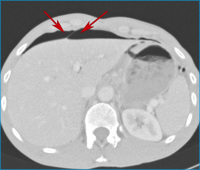

Abbildung 3: Die Rekonstruktion der CT-Bilder im sogenannten "Lungenfenster" zeigt anschaulich die Luftansammlungen in der Peritonealhöhle. Das Ligamentum falciforme der Leber ist von Luft umgeben (Pfeile).